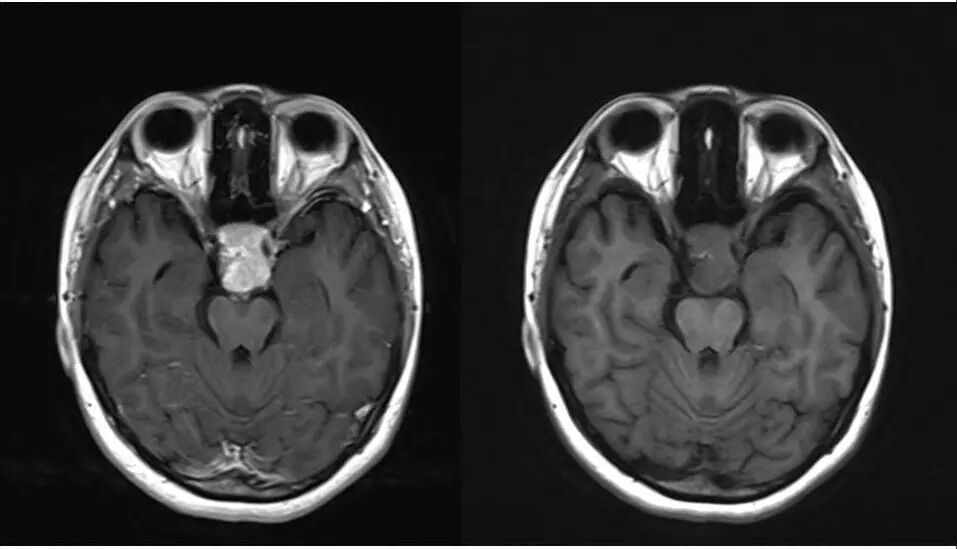

2.MR检查显示肿瘤位于鞍区,分叶状生长,呈稍长T2、稍长T1异常信号影,边界清楚,内部信号不均匀,其内可见“微囊”状异常信号影,视交叉受压上抬,DWI呈等或略高信号影,注药后呈不均匀明显强化;

4.重点观察冠状位:病变源于垂体偏左侧,与垂体界限不清楚,肿瘤偏右侧可见垂体与肿瘤之间裂隙,造成矢状位平扫及强化后误认为正常垂体存在,从而首先除外了垂体瘤,导致误诊;